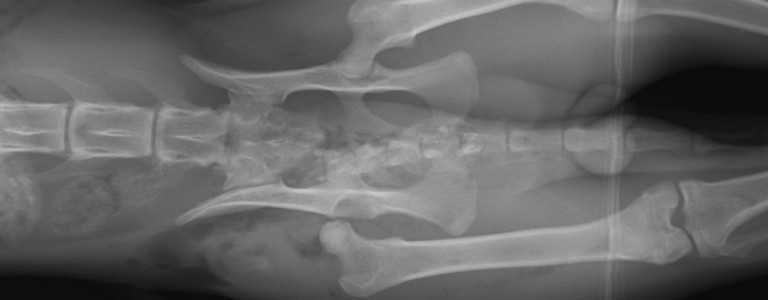

Diagnostic dysplasie